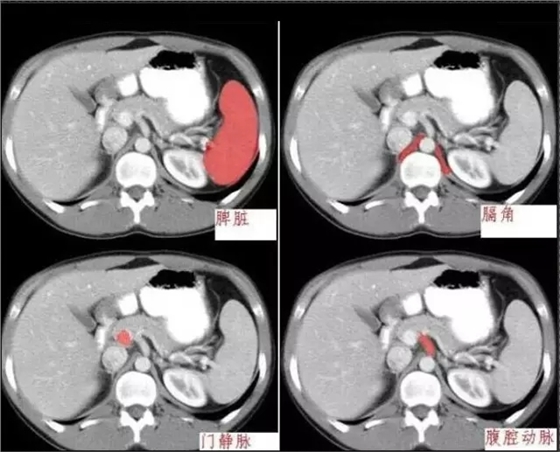

640.webp (4).jpg

640.webp (5).jpg